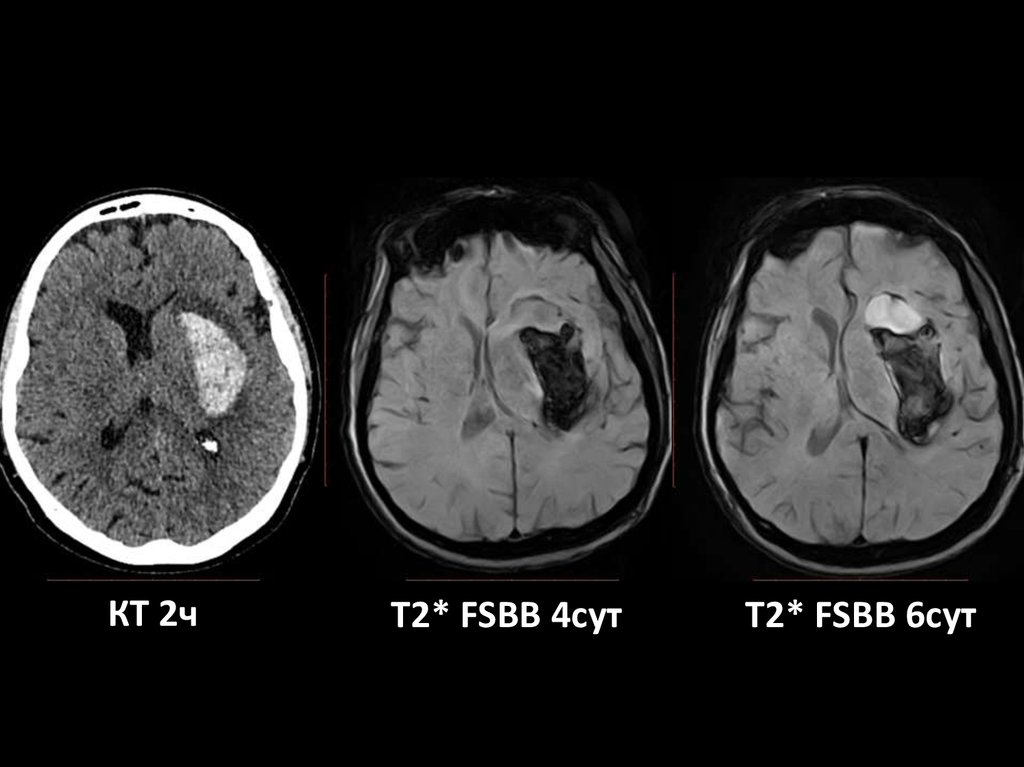

КТ 2ч

T2* FSBB 4сут

T2* FSBB 6сут

КТ

9.10.2015

2 часа после начала

64 HU